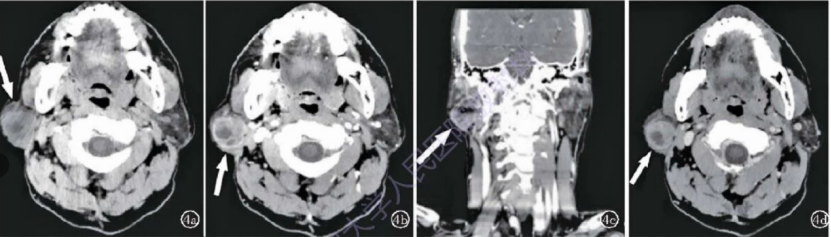

男,56岁,右腮腺BCA复发;肿块位于右侧腮腺浅叶区域,类圆形,边界清晰,平扫密度不均,中央可见囊变低密度区;动态增强肿块实质边缘明显强化,实质部分重度强化,静脉期持续强化